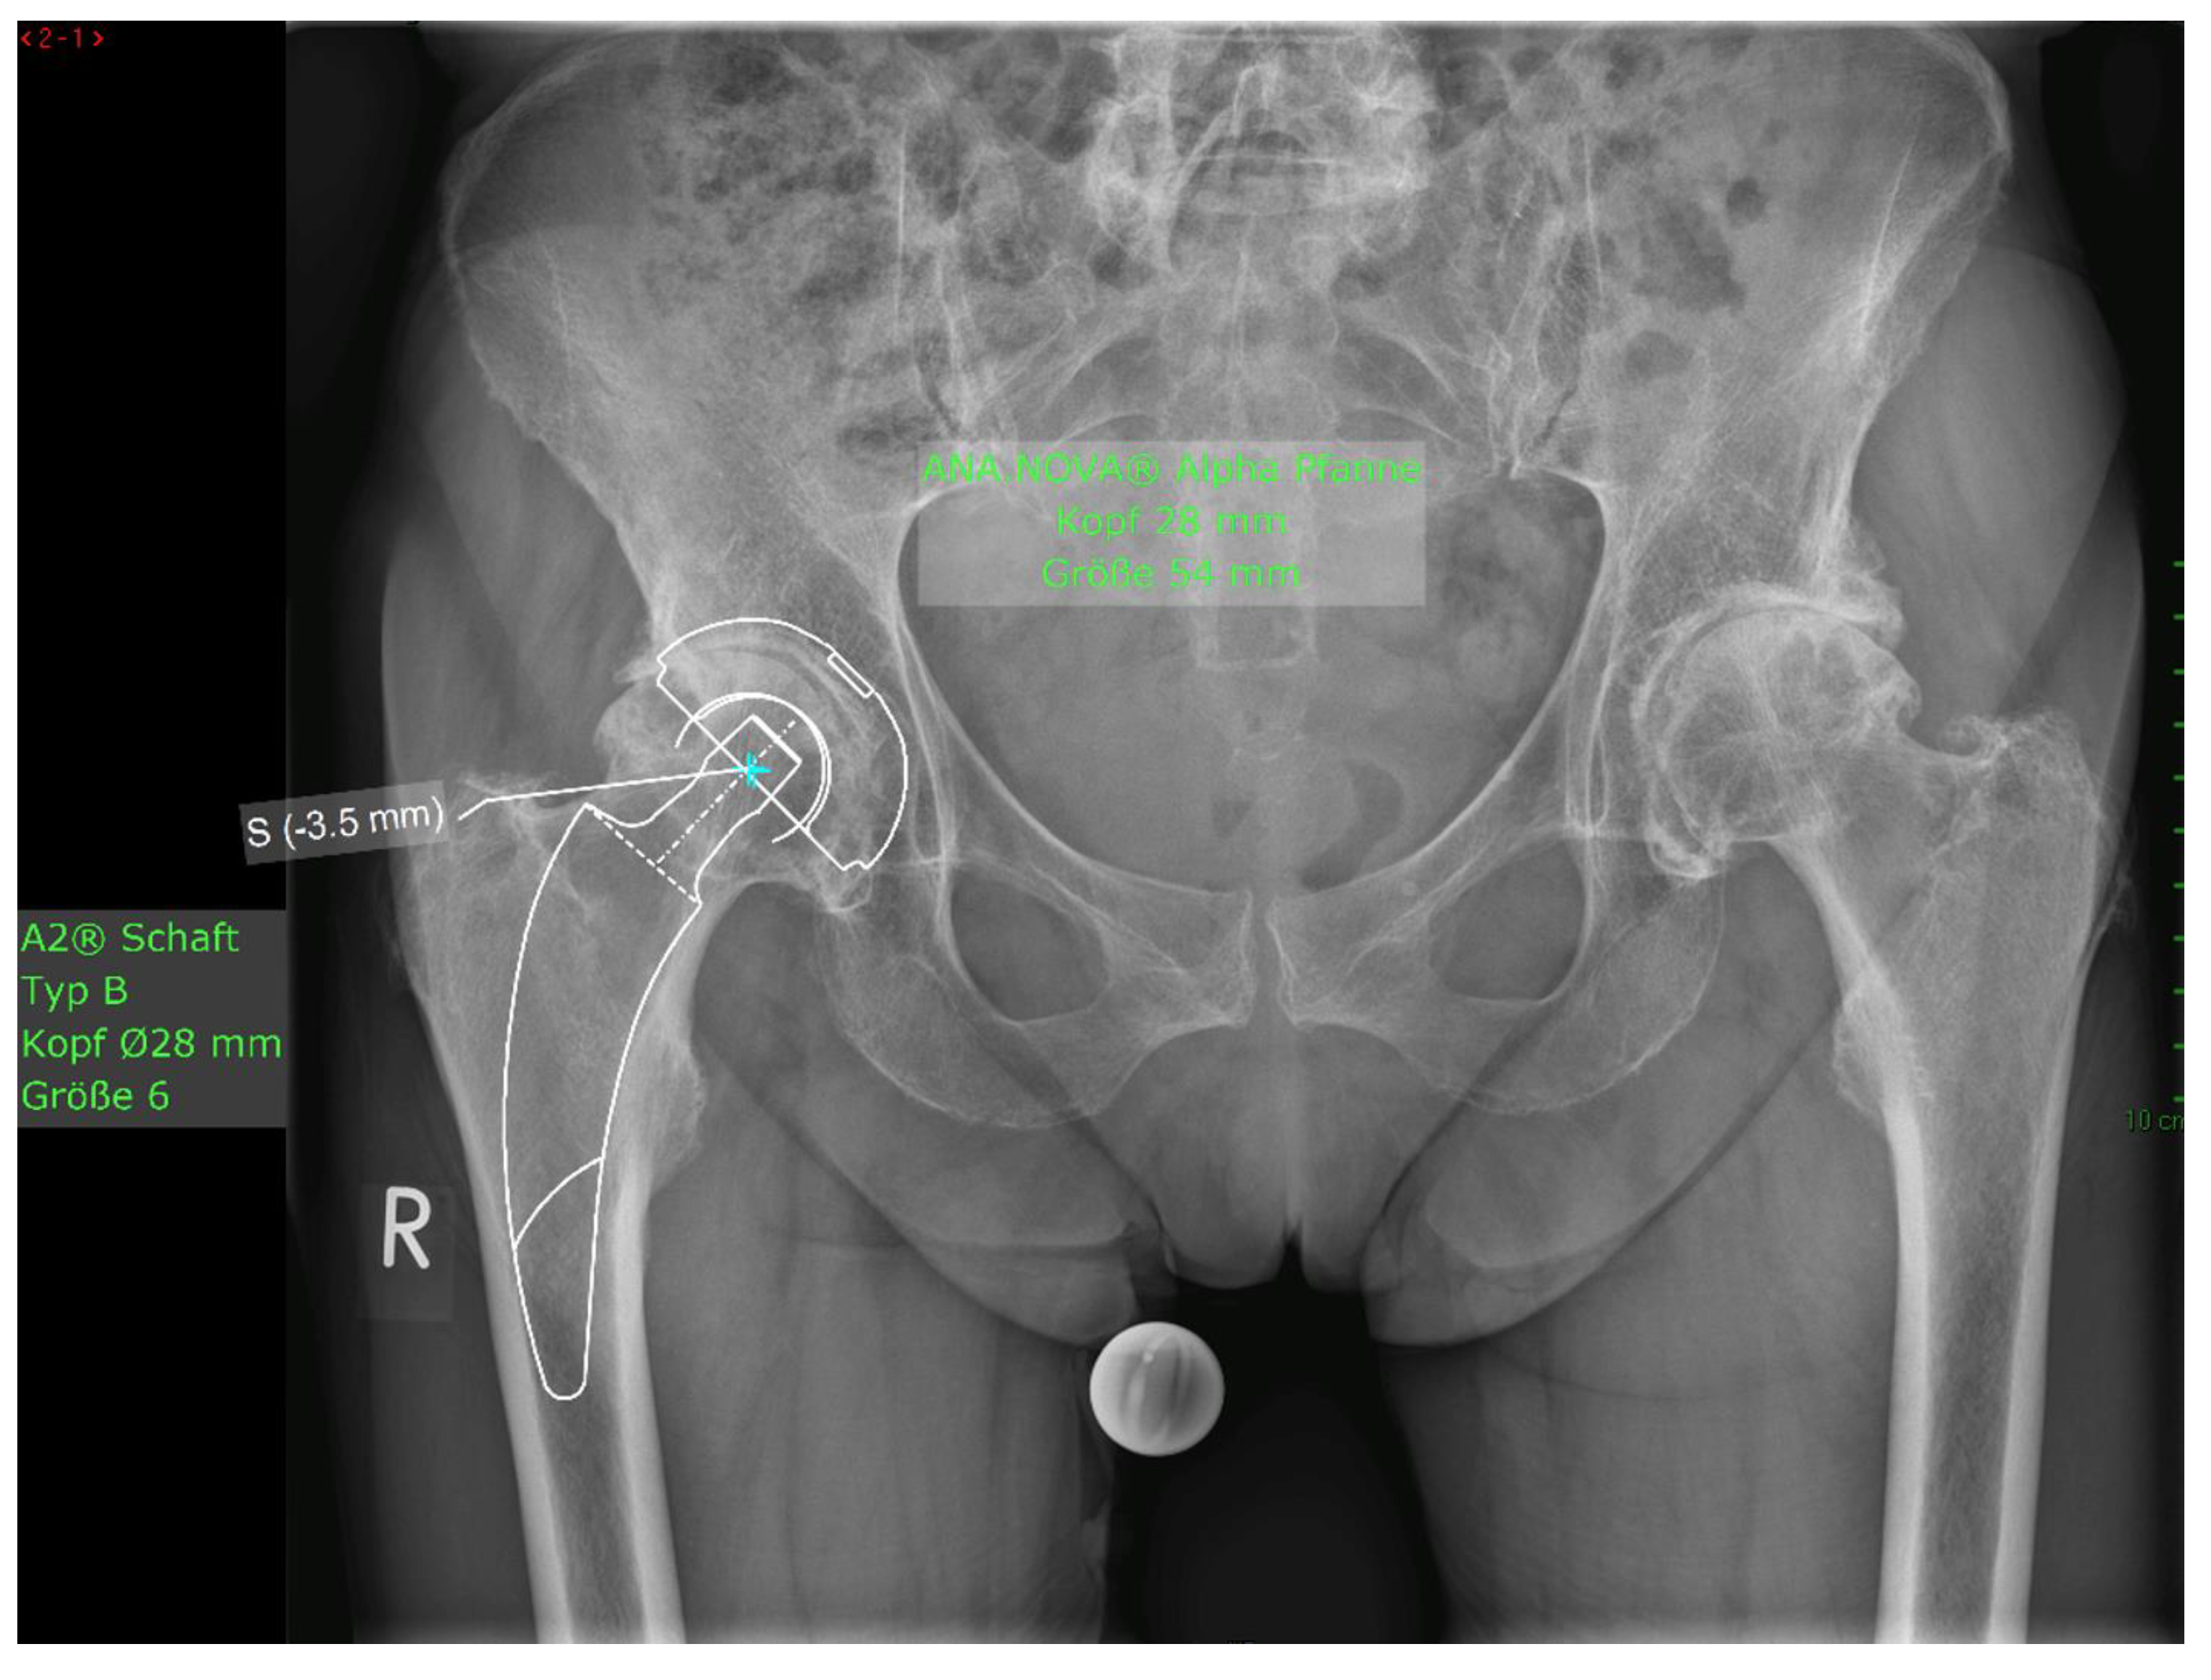

Of the 28 patients who underwent surgery, 5 withdrew their consent and 2 patients died due to unrelated causes. One prosthesis was explanted at 2 months postoperatively due to undersizing of the cement stopper, resulting in an inadequate cement mantle, which subsequently led to 14 mm of subsidence in the weeks following implantation. Hence, there were 20 patients with a 1-year follow-up. The mean HHS increased from 49.4 ± 13.9 preoperatively to 93.6 ± 6.9 at the final follow-up. No pain was reported by 19 patients at the final follow-up, with only occasional slight pain in one patient. The mean UCLA score increased from 3.5 ± 1.5 preoperatively to 5.1 ± 1.9 at the one-year follow-up. The mean HOOS-PS score increased from 44.2 ± 22.1 preoperatively to 60.0 ± 28.6 at the one-year follow-up. The FJS score was 68.3 ± 14.6 at the one-year follow-up. One patient experienced leg shortening of 10 mm. Periarticular ossification Brooker 1 was identified in three patients. One patient experienced axial subsidence of 2 mm. There were no postoperative infections. No radiolucent lines were observed, and none of the patients presented with osteolysis. A representative case is presented. Preoperative planning facilitated the achievement of anatomic restoration, as depicted in Figure Figure 3 demonstrates the correct postoperative positioning of the femoral stem and a complete cement mantle.

Figure 2. Figure Case #1 Female patient, 81 years old, with osteoporotic bone, coxa vara, and a Dorr C femur. Figure 2a Preoperative planning for a cemented A2 stem combined with a cementless ANA.NOVA Alpha Cup. The image shows good reconstruction of the leg length and offset. Figure 2b and Figure 2c. Postoperative anteroposterior (2b) and axial (2c) radiographic imaging 1 week postoperatively. Correct position of the stem and complete cement mantle.

Figure 4. a Case #3 Osteoarthritis, female, 81 years old, preoperative planning.

Preprints 111236 g004a